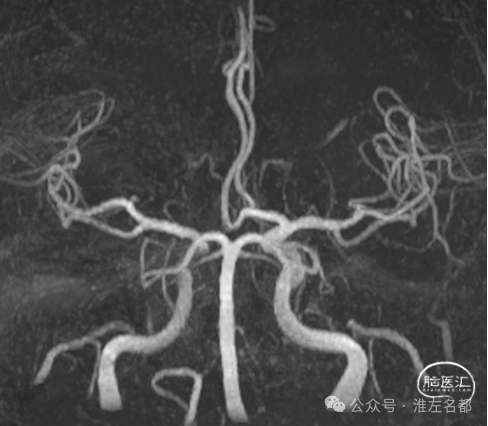

颅脑CTA:右侧大脑前动脉A2段局部管腔严重狭窄,右侧大脑前动脉A1段未发育,左侧大脑前动脉A1段粗大。

颈部CTA:所见脑供血动脉未见明确异常。

3D-TOF-MRA:右侧大脑前动脉A2段管腔未见明确异常。